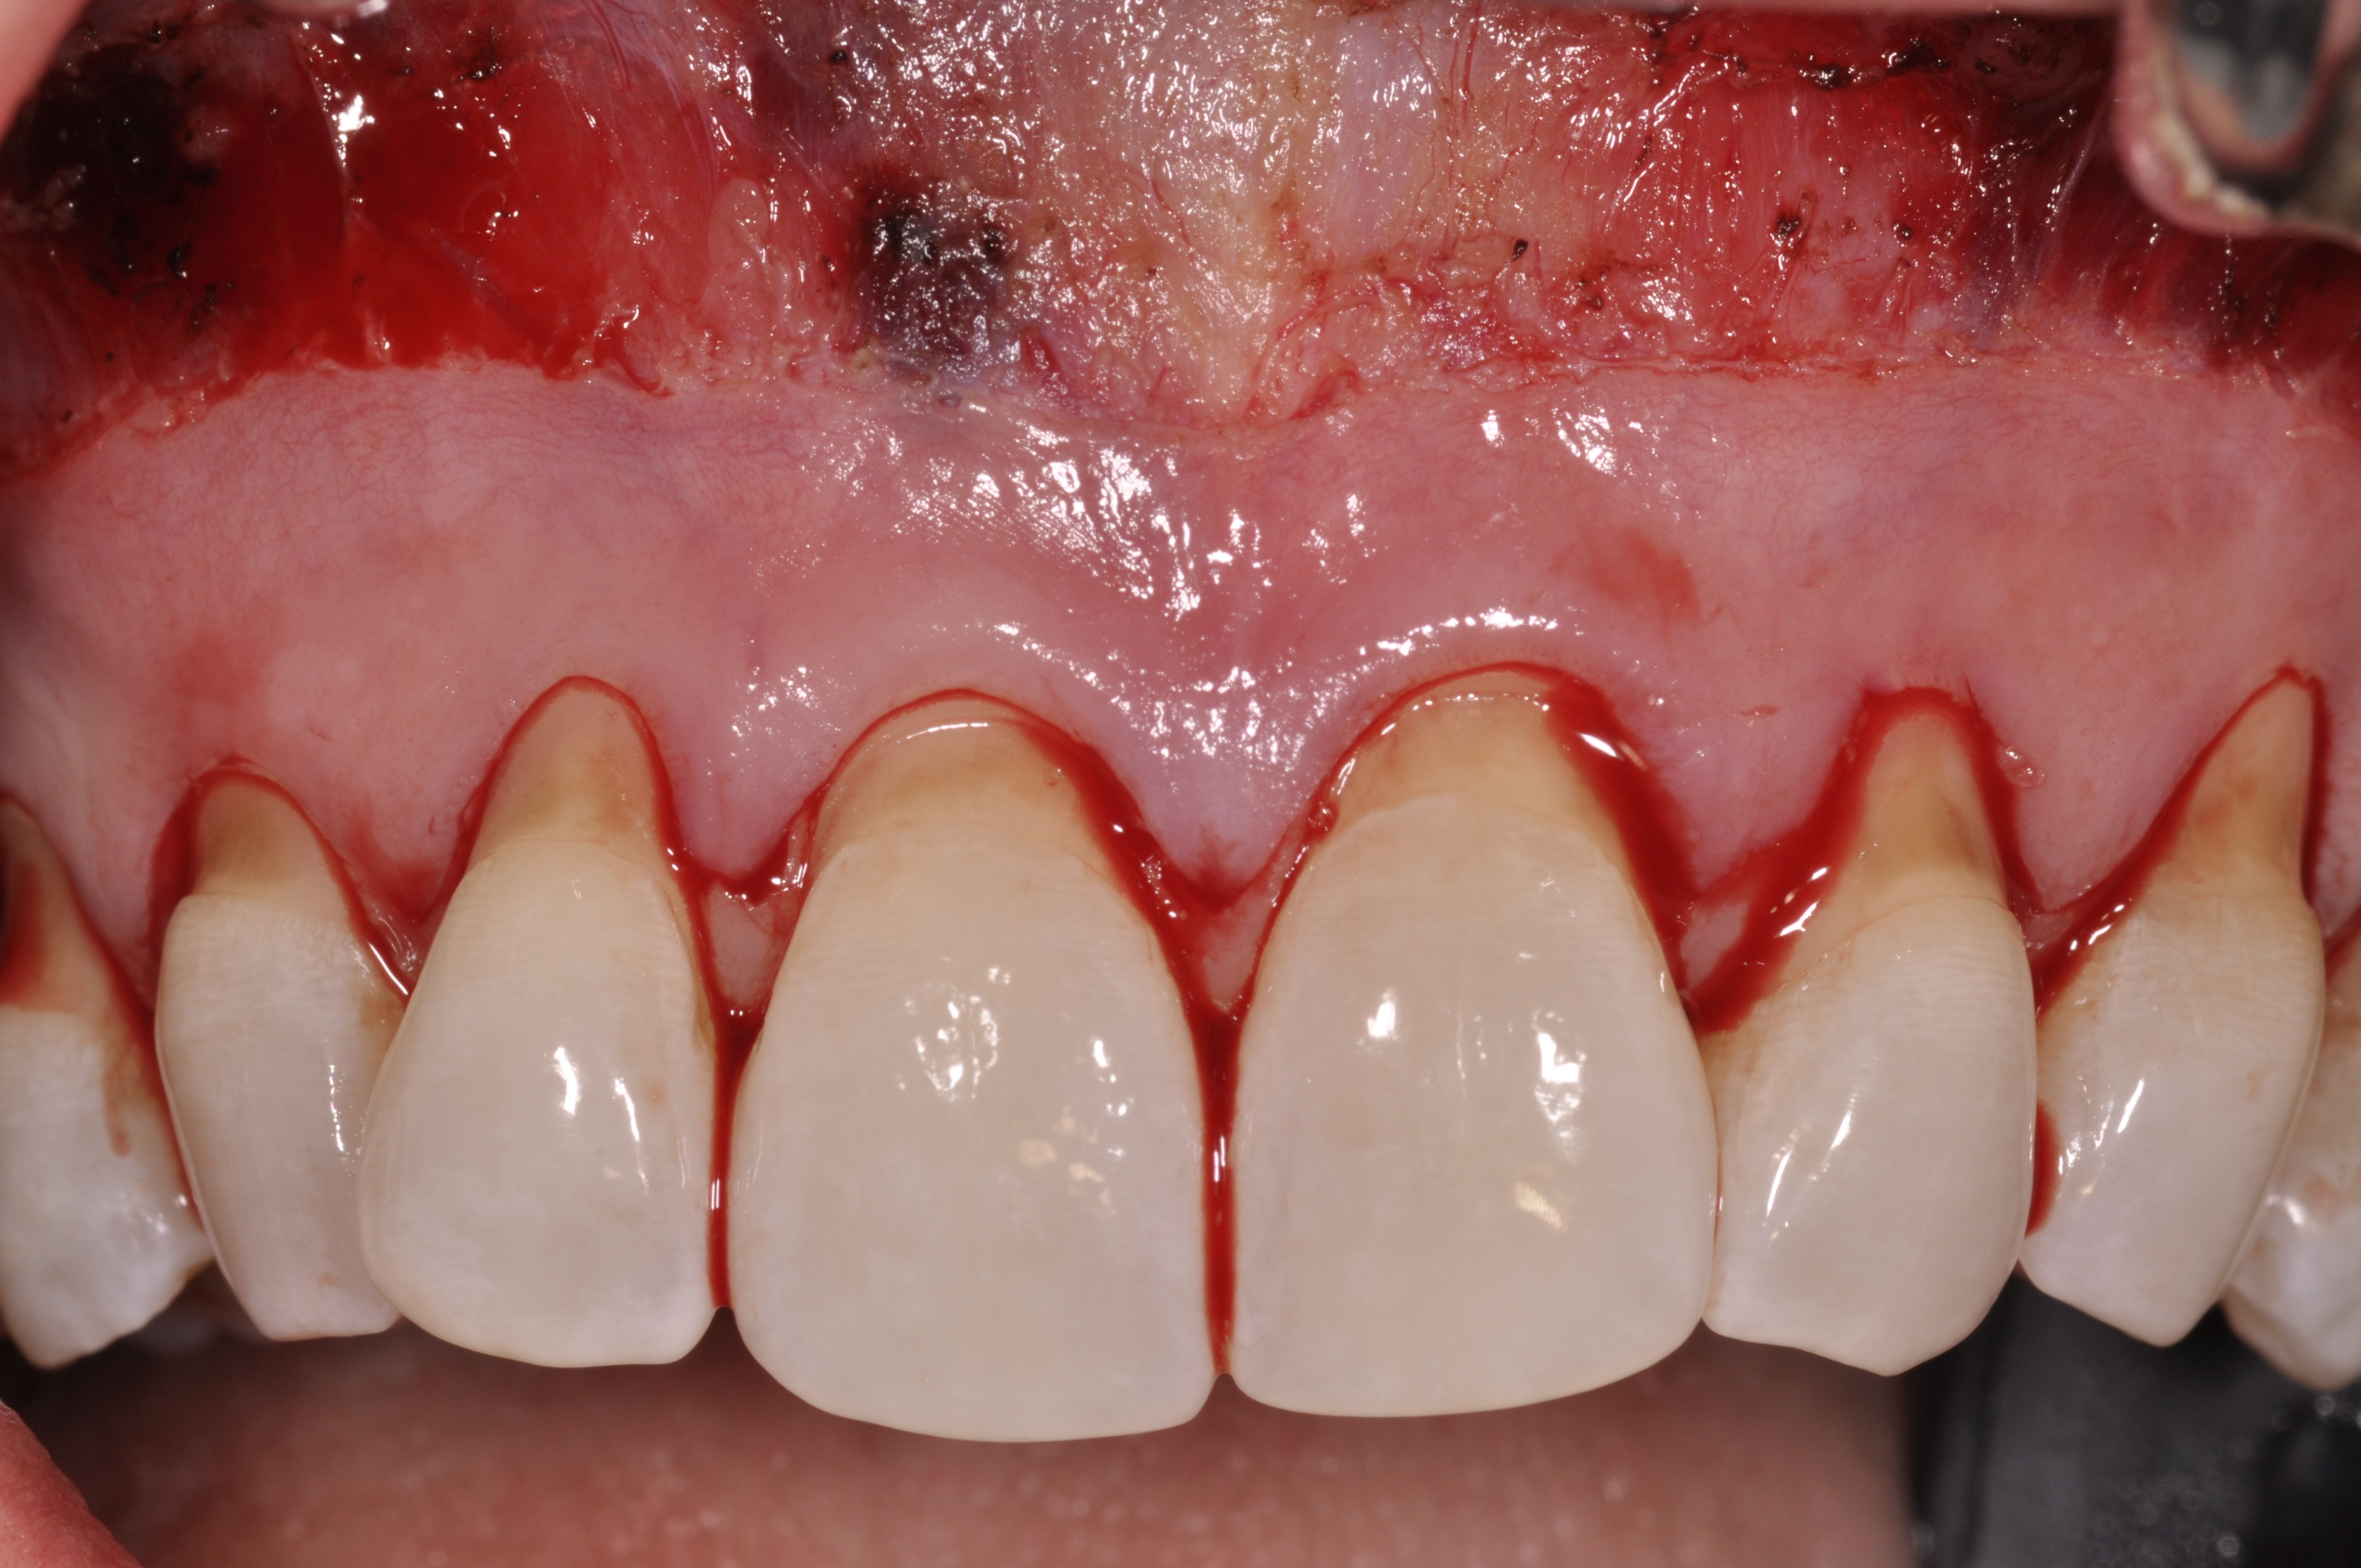

Fig 6. Pretreatment clinical view, maxillary left anterior sextant, of case presented.

Figure 6

Fig 7. Laser-assisted split-thickness vestibuloplasty performed.

Figure 7

Case Report

A 24-year-old, nonsmoking man presented for correction of gingival clefting and recession in the maxillary left anterior sextant (Figure 6). The patient’s medical history was noncontributory. After consultation and presenting various options to the patient to correct the localized recession, the patient opted for the use of acellular dermal matrix tissue rather than harvesting tissue from his palatal area.

After administration of an appropriate local anesthetic, a laser-assisted split-thickness vestibuloplasty was performed superior to the mucogingival junction from the right central incisor to the left first premolar region (Figure 7). Prior to any incisions being performed, a 20-mm x 40-mm dermal matrix graft (Puros Dermis), a 0.8-mm to 1.7-mm thick piece of tissue, was trimmed to appropriate length and width to correct the gingival defect present (Figure 8). The tissue graft was sized to 6 mm in height and spanned to the mesial line angle of the left central incisor to the distal line angle of the left canine area. The dermal matrix graft was rehydrated with the patient’s own platelet-rich plasma solution, which was harvested from 20 cc of whole blood collected immediately prior to the surgical procedure (Figure 9).